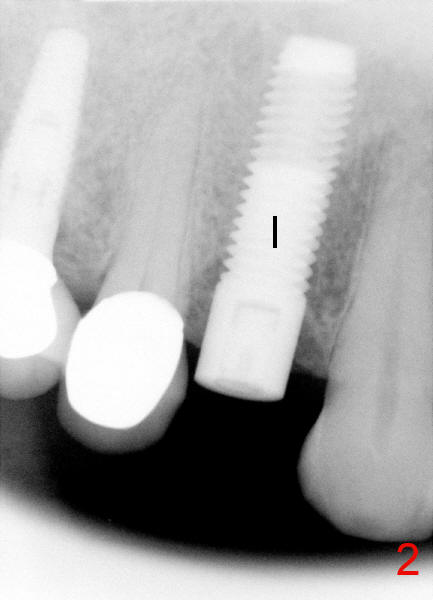

Sixty-eight year old healthy man has had multiple implants.  He readily accepted immediate implant when the tooth #5 had subgingival fracture of the lingual cusp (Fig.1).  A 5x20 mm Tatum screw implant was placed immediately after atraumatic extraction and bone expansion (Fig.2 I).  Implant rough surface was exposed buccally and lingually when the implant was placed equigingivally proximally.  Two buccal accessory incisions were made.  The flap was raised with scoring the periosteum underneath, advanced downward (as shown in Fig.3 arrow) and sutured to the lingual papilla.  The buccal aspect of the implant is covered, whereas the lingual rough surface remains partially exposed (Fig.4 arrow), assuming that the palatal mucoperiosteum is tough to advance even with release incisions.